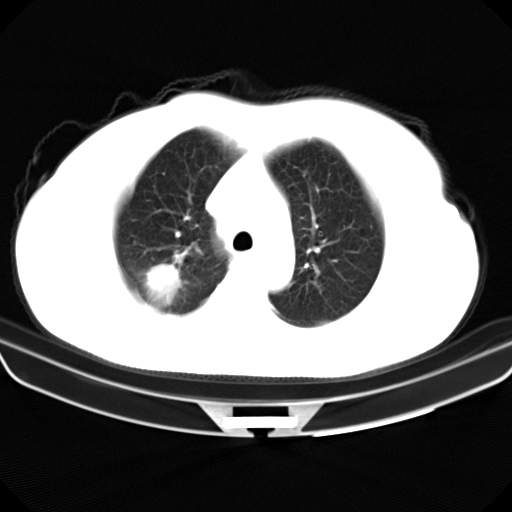

以下是引用zjzjr在2007-3-23 13:28:00的发言:[br]右肺上叶后段可见一结节状高密度影,可见毛刺征,胸膜凹陷征及血管导入征,纵隔内可见肿大淋巴结影.考虑右肺上叶周围型肺癌伴纵隔淋巴结转移.

以下是引用zjzjr在2007-3-23 13:28:00的发言:[br]右肺上叶后段可见一结节状高密度影,可见毛刺征,胸膜凹陷征及血管导入征,气管前腔静脉后可见肿大淋巴结影.考虑右肺上叶周围型肺癌伴纵隔淋巴结转移.